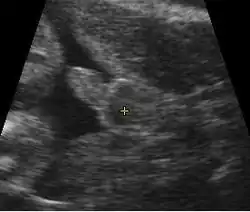

Contents in the cavity of the uterus seen at approximately 5 weeks of gestational age -

Artificially colored, showing gestational sac, yolk sac and embryo (measuring 3 mm as the distance between the + signs) -